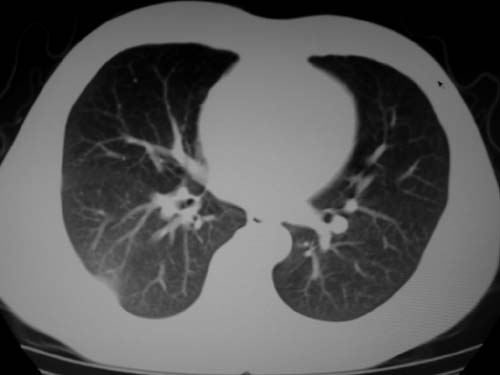

标题: CT19540: 31岁。自述结核性胸水治疗两个月后,在外院拍x线发 [打印本页]

标题: CT19540: 31岁。自述结核性胸水治疗两个月后,在外院拍x线发

右侧胸壁结节状软组织影伴相应肺叶内受侵,伴右侧胸腔积液。考虑:结核性可能大。

1、炎性包块;2、右侧少量胸膜积液。

1、炎性病变,结核可能;2、右侧少量胸膜积液。

病灶也是发生于结核球好发部位,支持结核

考虑结核性结节

多考虑包裹性胸腔识液。

右侧胸壁结节状软组织影伴相应肺叶内受侵,伴右侧胸腔积液,结合临床,首先考虑结核。

考虑结核性胸膜炎,胸膜肥厚,不除外胸膜间皮瘤可能,建议复查。

支持结核,胸膜间皮瘤不排除.

1)考虑右侧结核性胸膜结节。2)右侧胸膜增厚+包裹性胸腔积液。

结核性脓胸、肺内结核?